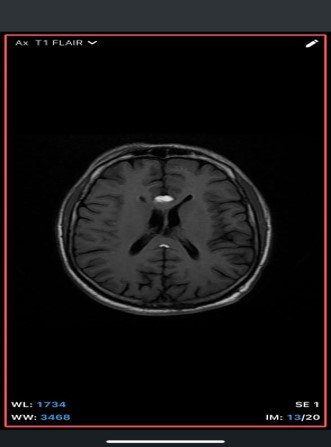

An extra-axial TI/T/Flair hyperintense lesion in midline at the inferior edge of the interhemispherie fissure extending along the superior margins of the corpus callosum with areas of blooming consistent with calcification and no post contrast enhancement –likely pericallosal lipoma.

• MRI

• T1-weighted: Hyperintense (fat signal).

• T2-weighted: Variable, usually hyperintense; may show chemical shift artifacts.

• Fat-suppressed sequences: Complete signal suppression confirms fat composition.

• Post-contrast: No enhancement.